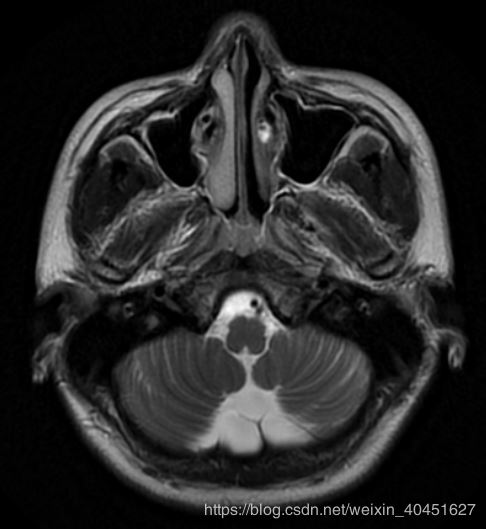

但真實的圖像是:

顯然顏色是有區別的.導致這種差別的原因是pyplot函數使用的cm也就是'color map' 是簡單的'bone' 并不能滿足醫學圖像的要求.